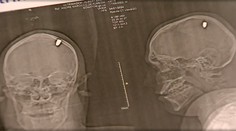

Zahraničné krimi Mladík žil štyri dni s guľkou v lebke. Vôbec o tom nevedel, myslel si, že ho trafil kameň Milan Špak 26. 1. 2024